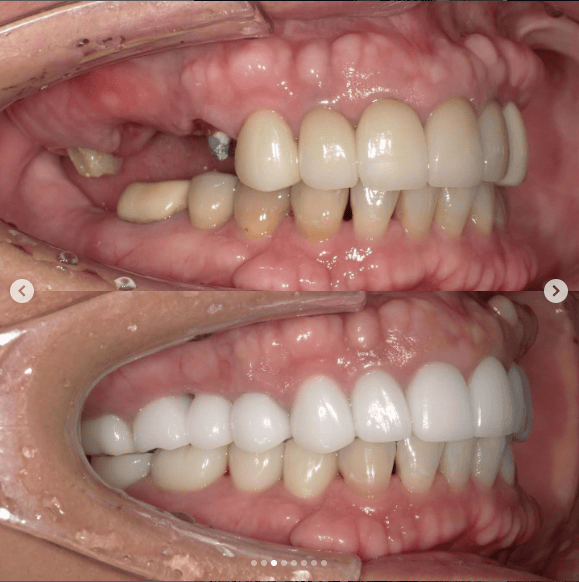

Case022 – インプラント

広島からの患者様です。

前歯を綺麗にしたい。インプラントをしたい。

という主訴で東京の歯医者をいろいろ調べて当院を選んでくださいました。

毎回、遠い中しっかり通ってくださり、選んで頂けた嬉しさと、その気持ちに応えたいという想いで診療させて頂きました。

前歯はご希望のお色でラミネートベニアでは出せない透明感のあるセラミックに上下左側7はインプラントをさせて頂きました。

左上は破折で温存不可。

骨も少なかったので、サイナスリフトも行い計五回の来院で被せ物を入れさせて頂きました。

左下は前回のクリニックでの埋入位置が深すぎて食べカスも毎回詰まる、セルフメンテナンスではら汚れも取れない。インプラント周囲炎にもなっていたので、一度前のインプラントを除去し、そこから新しくインプラントを埋入し、診療させて頂きました。

インプラント、歯並び、審美歯科にご興味のある方はいつでも相談にお越しください。

担当 理事長 佐藤 悠野